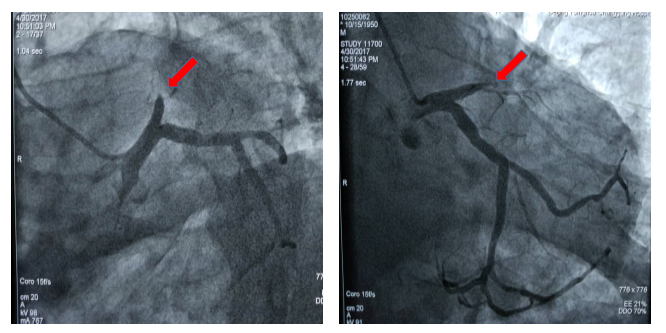

图1 患者术前冠脉造影显示冠脉血管前降支近段100%闭塞

图2 患者术后冠脉造影显示冠脉血管前降支支架治疗后完全开通